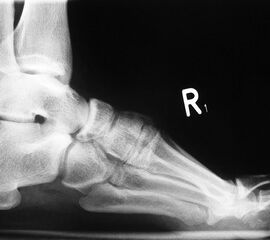

• Fuß belastet dp und seitlich (Abb. 14 und 15)

Typische Merkmale der Standard-Seitaufnahme des Fußes im Stand

• Knöchelgabel ist außen rotiert

• Talus und Calcaneus verlaufen fast parallel

• Sinus tarsi ist einsehbar

• Subtalare Gelenklinie verläuft horizontal und ist breit einsehbar

• Der Abstand Malleolus medialis zum Os naviculare ist verkürzt

• Der Calcaneus erscheint verkürzt

• Der Krümmungsscheitel des Fußes ist erhöht

• Calcaneus pitch ist meist erhöht, der Rückfuß Equinus ist eher selten 12